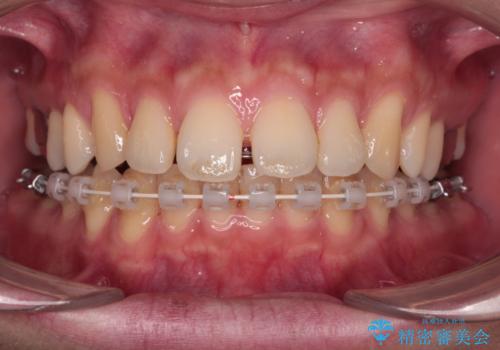

- 矯正装置

- ハーフリンガル

インビザラインは自己管理が煩わしく、表側のワイヤー装置は目立つので避けたいとのことで、上顎だけが裏側装置のハーフリンガルにて矯正治療を行うこととしました。

矯正治療中に結婚式があったそうですが、隙間も改善しており、一部装置を外すことなく挙式できたとのことでした。